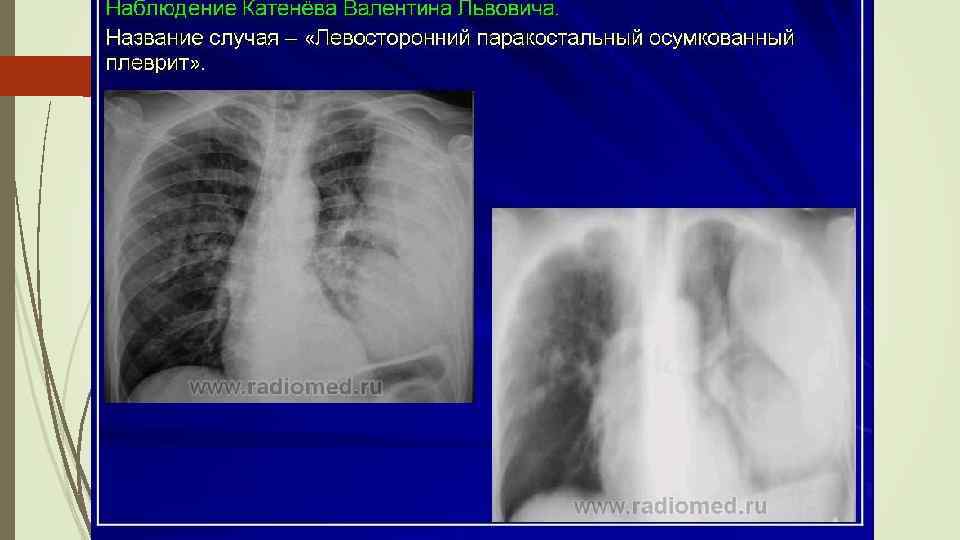

Осумкованные плевриты: а) пристеночные (паракостальные) осумкования, прилежащие широким основанием к поверхности ребер; б) верхушечные (апикальные) осумкования; в) диафрагмальные (базальные) осумкования, расположенные между основанием легкого и диафрагмой; г) междолевые (интерлобарные) осумкования, расположеные между долями легких; д) парамедиастинальные осумкования, расположенные в заворотах парамедиастинальной плевры.

Осумкованные плевриты: а) пристеночные (паракостальные) осумкования, прилежащие широким основанием к поверхности ребер; б) верхушечные (апикальные) осумкования; в) диафрагмальные (базальные) осумкования, расположенные между основанием легкого и диафрагмой; г) междолевые (интерлобарные) осумкования, расположеные между долями легких; д) парамедиастинальные осумкования, расположенные в заворотах парамедиастинальной плевры.